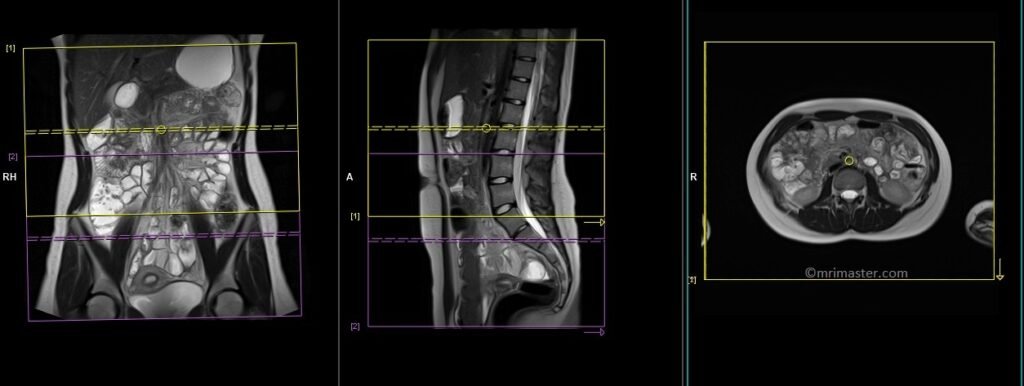

T2 TRUEFISP axial

Plan the axial slices on the coronal image, position the block horizontally across the abdomen as shown, and ensure that the positioning block is also checked in the other two planes. Establish an appropriate angle horizontally across the abdomen in the sagittal plane. The slices must be sufficient to cover the entire abdomen and pelvis from the stomach to the pubic symphysis. Phase oversampling can be used to avoid wrap-around artifacts. Instruct the patient to hold their breath during image acquisition.

The axial scan is performed as two separate blocks with a 20-30% slice overlap between them. The scan is performed this way to avoid any RF inhomogeneity-related artifacts by conducting the scans at the isocenter of the magnet. Use the composing function in the scanner to stitch the two blocks together.

Protocol Parameters TRUEFISP axial

TR 4-5 | TE 2-3 | FLIP 60 | NEX 1 | SLICE 4 MM | MATRIX 320×256 | FOV 350-400 | PHASE A>P | OVERSAMPLE 50% | IPAT ON |